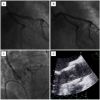

It should be reminded that alleviating the aortic stenosis will theoretically improve coronary haemodynamics by increasing the driving coronary pressure and decreasing the metabolic needs of the myocardium (especially in the case of combined aortic stenosis and regurgitation). Therefore, there is a general consensus to disregard the presence of coronary stenoses in TAVI candidates when (1) angina is not the dominant symptom of the patient, and (2) there is no critical stenosis in the left main (LM), the proximal LAD or in the proximal dominant RCA/LCx. In case a revascularisation procedure is deemed necessary, the latter will be carried out prior to the TAVI intervention, which can be performed under dual antiplatelet therapy. Figure 2 shows a case of staged hybrid approach combining PCI and TAVI (see figure legend).

So far, the intentional combination of a PCI and port access endoscopic mitral valve repair has been performed in 43 patients in the OLV Clinic. After a mean follow-up of 28.8+/-25 months one non-cardiac death was reported, an endoscopic re-operation for mitral valve replacement was needed and two new PCI were registered, one being target vessel revascularisation. Figure 3 illustrates the case of a combined endoscopic mitral valve repair and PCI of the LAD (see figure legend).

COMBINED TAVI AND ENDOSCOPIC VALVULAR SURGERY

More complex combinations of surgical and interventional procedures have recently been performed. These approaches are technically not particularly complicated but they illustrate the importance of an outstanding team approach including optimal logistical aspects. Two such examples are presented as follows in Figure 4 and Figure 5 . In the first patient PCI was followed by a TAVI and port access endoscopic mitral repair, all procedures being staged. In the second patients, port access mitral repair and transapical TAVI was performed during the same session. For details see the figure legend.